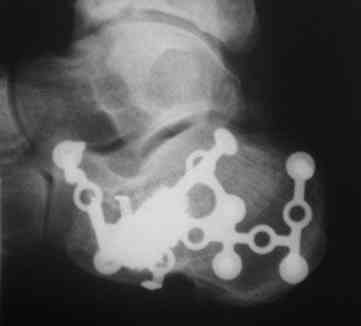

Re: перелом пяточной кости

Из личного опыта, кстати после снятия кортикальной створки, репозицию удобно делать роторасширителем.